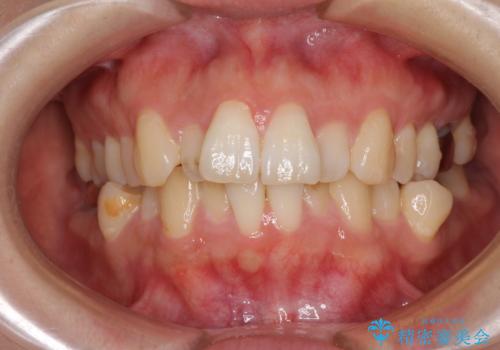

- 前歯のデコボコを気にして来院された患者様です。

非抜歯矯正にて治療を行うと、仕上がりで口元が突出する可能性があったため、小臼歯抜歯での矯正治療を行うこととしました。

上顎は左右の第一小臼歯2本を、下顎は左右の第二小臼歯2本を抜歯して、口元が突出しないようにしながら、奥歯の咬み合わせを改善していく治療計画としました。

目立たない装置が希望であったため、上顎が裏側装置である、ハーフリンガル装置を選択されました。